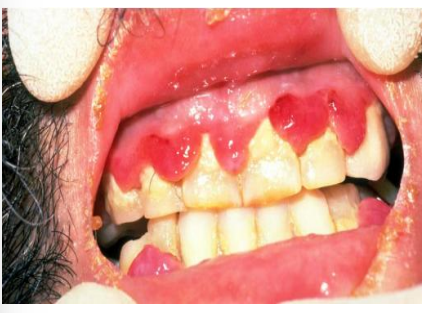

Scurvy (vitamin C deficiency)

Scrobutic gingivitis